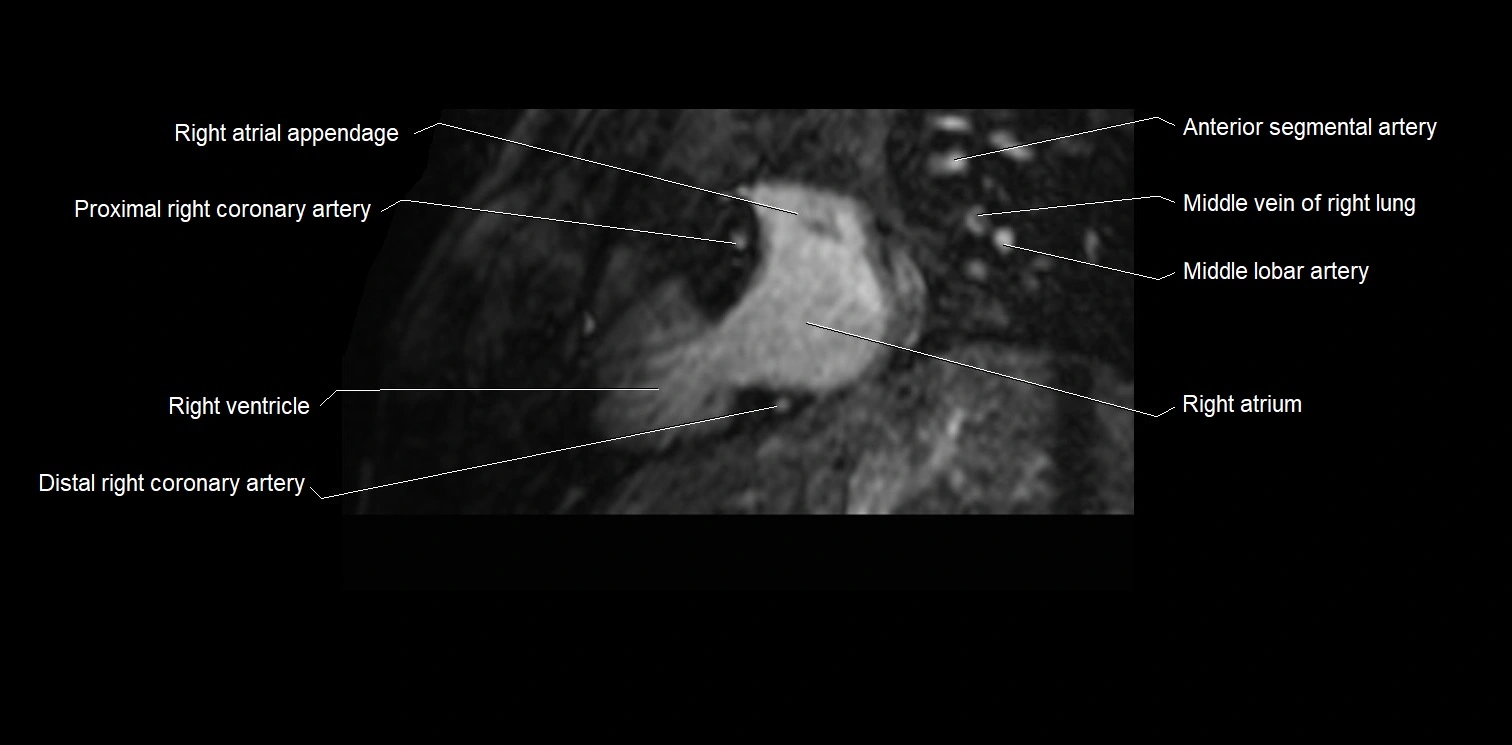

MRI image